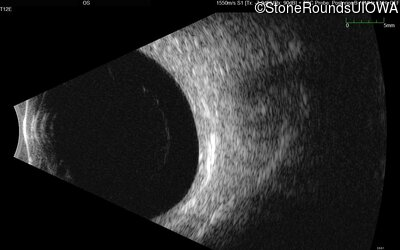

B-Scan Ultrasonography - Right - Light Perception

Exemplar